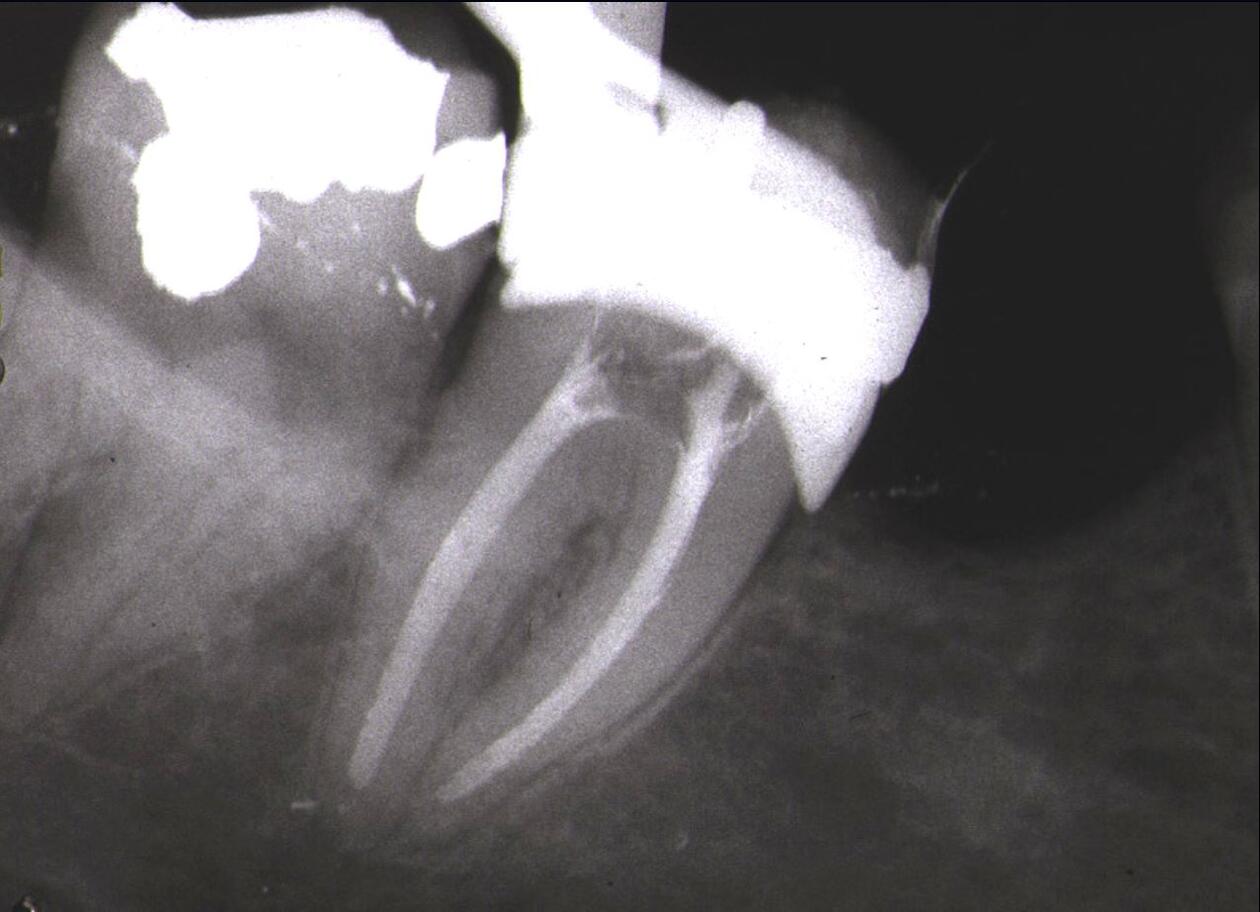

Rotfylling av tenner

Vi tilbyr rotbehandling, også kjent som rotfylling, av tenner.

Rotbehandling er en god behandling for å bevare tenner med betennelse eller med svekket krone. Selv om den synlige delen av tannen kan være nesten borte kan bevaring av roten være en rimeligere og bedre løsning enn kunstige tenner.